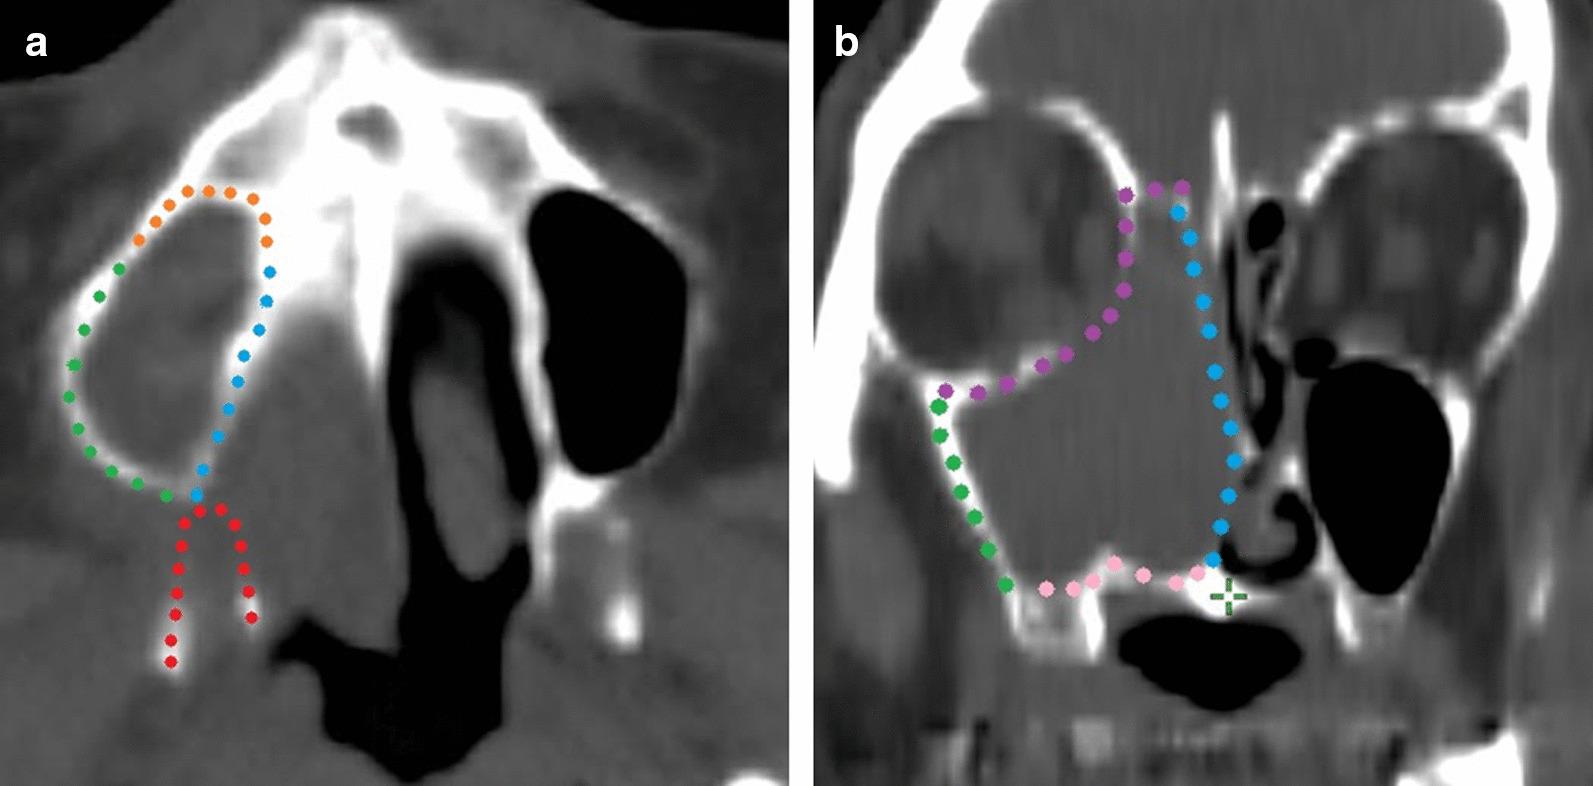

The aim of this study was to evaluate the long-term treatment results of combined superselective intraarterial chemotherapy and radiation therapy for advanced maxillary sinus cancer (MSC) and the incidence of regional lymph node failure, and to reveal the clinical and anatomical predictive factors for metastasis.

We retrospectively evaluated 55 consecutive patients with locally advanced squamous cell carcinoma of the maxillary sinus who were treated with external radiotherapy and superselective intraarterial chemotherapy. Elective nodal irradiation (ENI) was performed only in the clinical node-positive (cN+) cases and not in the clinical node-negative (cN0) cases.

Thirty-eight patients were cN0, and 17 were cN+ at diagnosis. Regional lymph node metastases occurred in 7 of 38 patients with cN0, and 2 of 17 with cN+ during the median follow-up period of 36 months. There were more cases of high-grade (3 or 4) late adverse events in the ENI group than in the non-ENI group (13% vs. 41%, respectively; p = 0.03). In cN0 cases without ENI, invasion of the pterygoid plates (57% vs. 90%; p < 0.01) and oral cavity (35% vs. 92%, with invasion vs without invasion, respectively; p = 0.02) was significantly correlated with a low 5-year regional recurrence-free rate.

Patients with MCS and invasion of the pterygoid plates and oral cavity can be considered appropriate candidates for ENI.

本研究旨在评估联合超选择性动脉内化疗和放疗治疗晚期上颌窦癌(MSC)的长期治疗效果和区域淋巴结失败的发生率,并揭示转移的临床和解剖预测因素。

我们回顾性评估了 55 例接受外部放疗和超选择性动脉内化疗的局部晚期上颌窦鳞状细胞癌连续患者。选择性淋巴结照射(ENI)仅在临床淋巴结阳性(cN+)病例中进行,而不在临床淋巴结阴性(cN0)病例中进行。

38 例患者为 cN0,17 例患者为 cN+。在中位随访 36 个月期间,7 例 cN0 患者和 2 例 cN+患者发生区域淋巴结转移。ENI 组发生高级(3 或 4 级)晚期不良事件的病例多于非 ENI 组(分别为 13%和 41%;p=0.03)。在未行 ENI 的 cN0 病例中,翼板侵犯(57%比 90%;p<0.01)和口腔侵犯(35%比 92%,有侵犯与无侵犯相比;p=0.02)与 5 年区域无复发生存率较低显著相关。

翼板和口腔侵犯的 MSC 患者可考虑行 ENI。